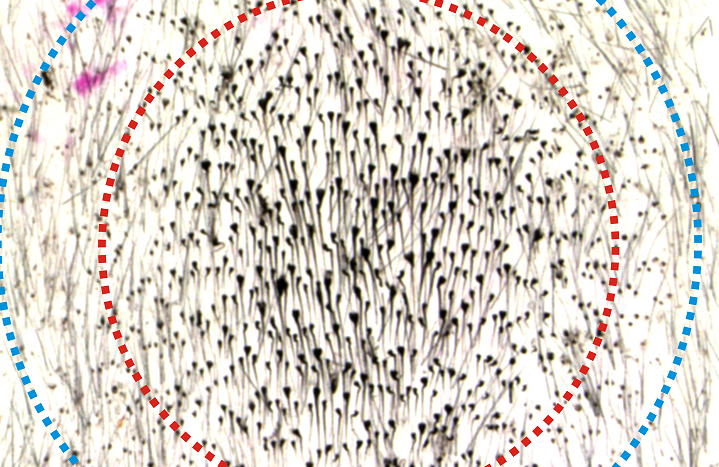

На силу аварийных сигналов больше всего влияет конфигурация выдергиваемых волосков, выяснили ученые. Они вырывали 200 фолликул, один за другим, со спин лабораторных мышей — в различных вариантах расположения. При низкой концентрации ранок восстановления волос не происходило. Однако при выдергивании фолликул с круглых участков (3-5 миллиметров в диаметре) вырастало от 450 до 1300 волосков, и процесс выходил за рамки изначально заданной зоны.

По мнению авторов исследования, волосяные луковицы не просто реагируют на выдергивание, но и коммуницируют между собой. Биологи называют это явление бактериальным чувством кворума: микроорганизмы принимают коллективное решение о требуемой интенсивности иммунного ответа. При выдергивании луковиц с большой территории сигналы слишком слабы для массового решения.